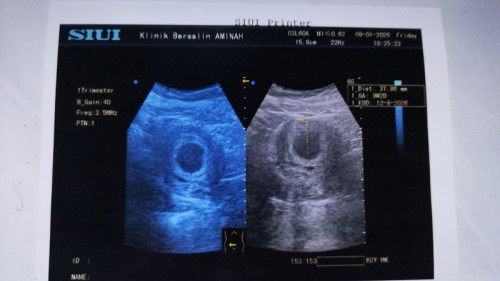

Baru usg karena ada flek sedikit (bintik kecil) kecoklatan karena kemarin habis kegiatan seharian full, mlemnya sempet sakit perut bagian kanan (klau berdiri) jd tak buat tiduran Alhamdulillah lebih rileks dan gak sakit lagi. Nah kata dokter usia kehamilan 9-10 weeks. Dan masih kantong saja jdi di vonis BO. Ada yang prnh ngalamin gak? Klaau usia kehamilan 9-10 weeks adakah kemungkinan bakal ada janin? Soalnya juga baru usg perut saja, blm usg transvagina. #mohonbantujawabbundaBunda2 #Sharingdong_Bund #bantujawab #firstmom #sharing #askmommies #Needadvice